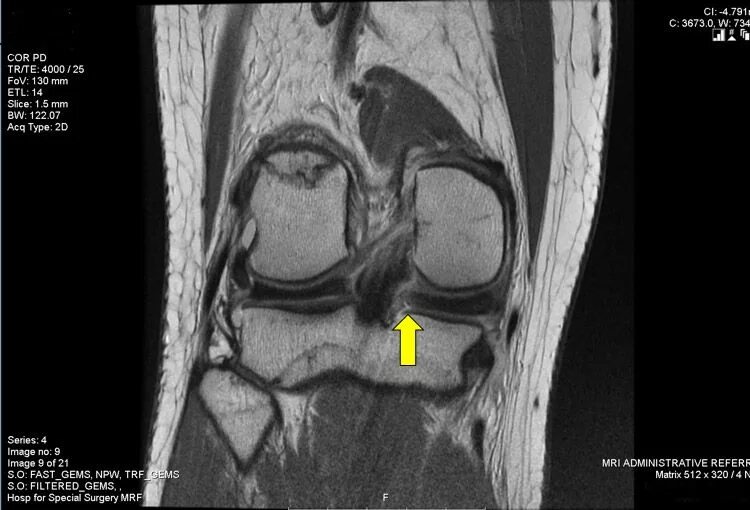

Повреждение мениска мрт